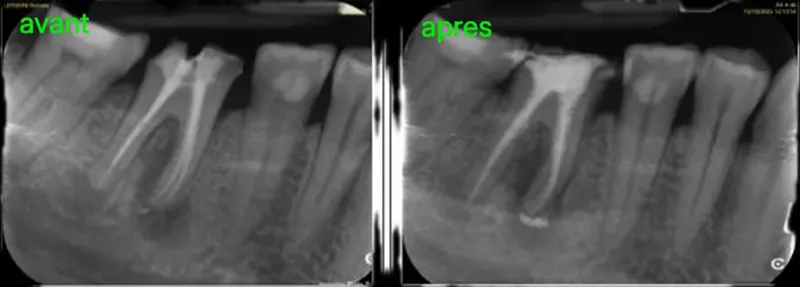

Le traitement endodontique : sauver la dent de l’intérieurLe traitement endodontique, plus couramment appelé traitement de canal ou dévitalisation, consiste à préserver une dent infectée ou inflammée en traitant les tissus situés à l’intérieur de la racine, dans ce qu’on appelle le canal pulpaire.

- Ou encore lorsqu’il est nécessaire de retraiter un canal après un ancien soin devenu défectueux.

- Obturation tridimensionnelle des canaux à l’aide d’un matériau biocompatible (la gutta-percha).

Avec les technologies modernes (microscope opératoire, instruments en nickel-titane, radiographie numérique 3D), les traitements endodontiques sont aujourd’hui fiables, indolores et durables.